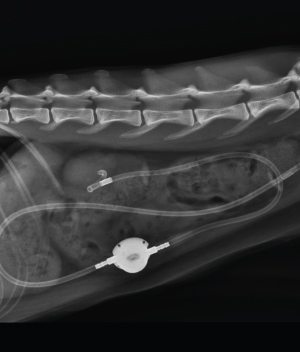

Subcutaneous Ureteral Bypass

(SUB, 피하 요관 우회술)

요관 결석이 있는 경우 시행할 수 있는 최신 중재술입니다.

고양이 요관 결석 증상에 우선적으로 지시되며 다른 중재술에 비해

수술 시간이 짧고 예후가 좋습니다.